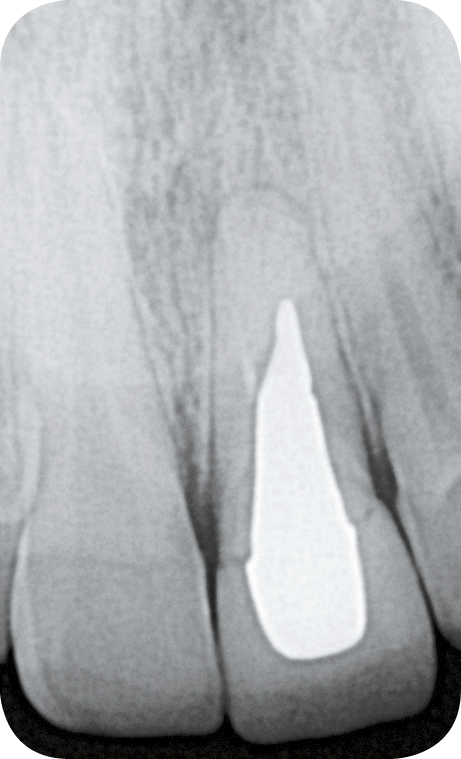

L’examen clinique révèle la présence d’un biotype parodontal épais, une gêne lors de la palpation vestibulaire ainsi qu’une douleur à la percussion. La réalisation d’une radiographie rétro-alvéolaire et d’un CBCT confirme la présence d’une fissure radiculaire (fig. 2).